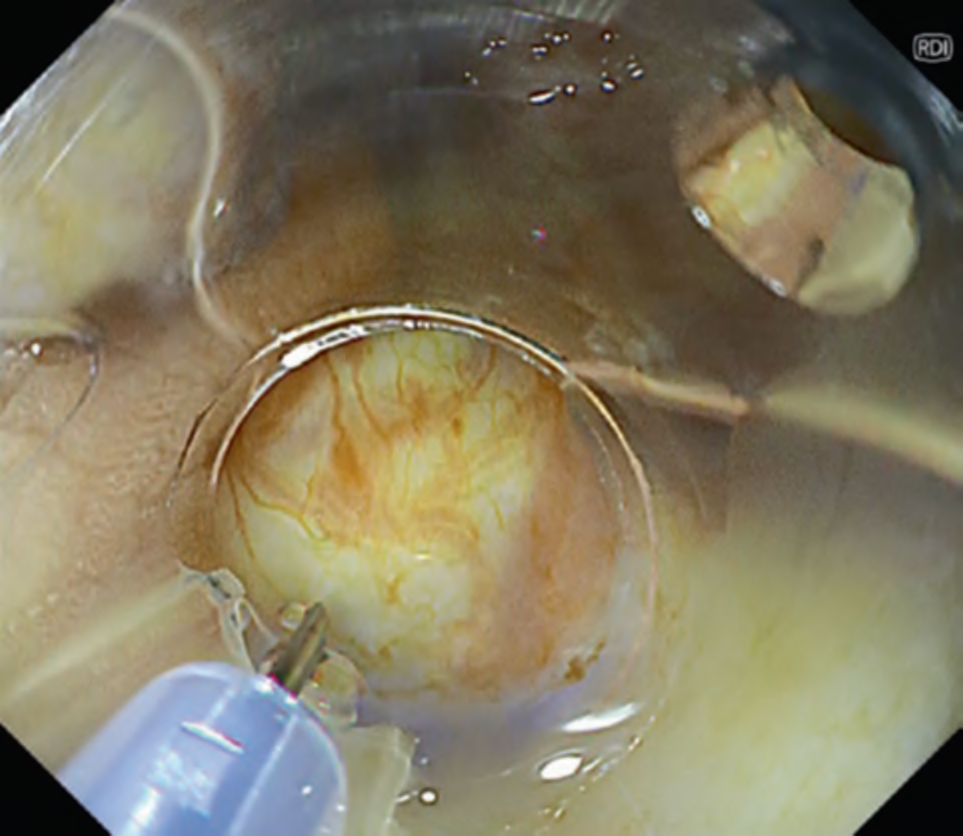

This mode is developed aiming improvement of visualization of deep blood vessels. Compared to mode 1, mode 2 enhances redness of blood vessels and improves the visibility of blood vessels in deep tissues. This is especially useful for initial submucosal injection during endoscopic submucosal dissection (ESD). Normally, when performing injection during ESD, blind injection cannot be avoided, because we cannot directly observe blood vessels below the mucosa. However, by identifying deep blood vessels under RDI mode 2 and avoiding unnecessary injury of those vessels, it prevents bleeding or the submucosal hematoma formation (. Figs. 6 and 7) [7]. Similarly, this mode is also reported to be useful for predicting the depth of esophageal varices and confirming red color signs [8].

Fig. 6 Scene of injection using RDI mode 2 in rectal ESD with abundant hemorrhoids, avoiding the blood vessels